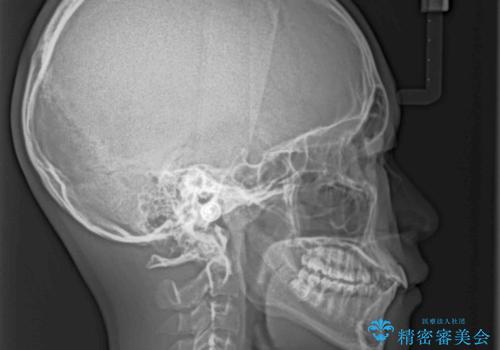

下顎前歯が上顎前歯を突き上げるような咬み合わせとなっており、その影響で上顎正中に隙間ができている状態でした。

突き上げによる隙間を予防する為に、深い咬み合わせを改善するような治療計画としました。咬み合わせを改善させることはできましたが、隙間は後戻りしやすいので、通常の下顎前歯のみではなく、上顎前歯2本もワイヤーで保定を行いました。